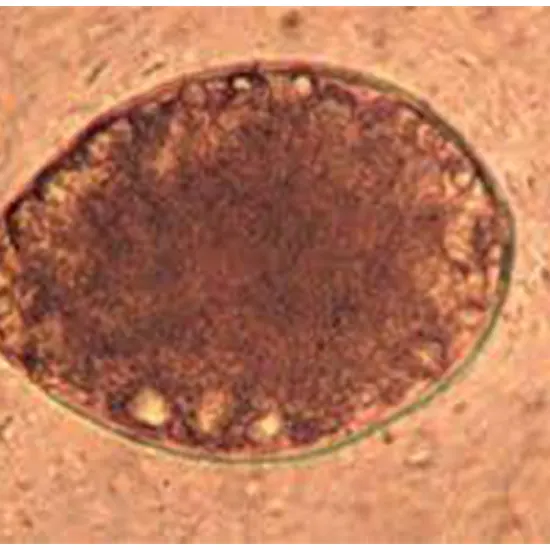

Diagnosis of diphyllobothriasis typically involves identifying the tapeworm or its eggs in stool samples. Laboratory testing, such as microscopy or molecular testing, may be used to confirm the presence of Diphyllobothrium spp. eggs or segments in the stool. Sometimes, segments of the tapeworm may also be visible in the stool or vomit of infected individuals.